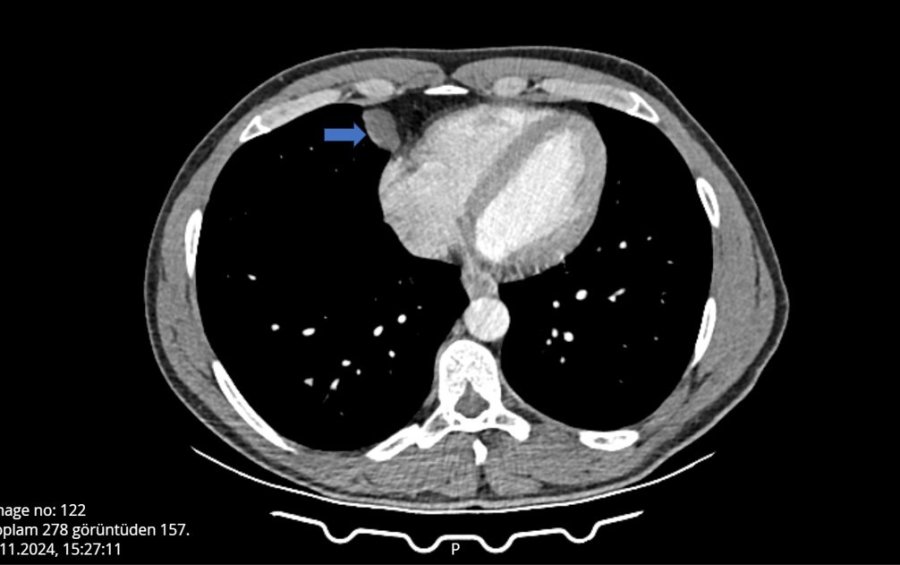

Antalya'da yaptığı seyahat dönüşü öksürme ve hapşırma krizlerine tutulup girip olduğunu düşünen yat kaptanı hastaneye başvurdu, yapılan kontrolde akciğer ve kalp arasında kist olduğu tespit edildi. Ameliyata alınan kaptan, Video Yardımlı Torakoskopik Cerrahi (VATS) ile 10 dakikalık operasyon sonucu sağlığına kavuştu.

Yat kaptanlığı yapan 45 yaşındaki Ömer Can, çıktığı uzun seyahat sonrası omuzunda ağrı hissetti, öksürük ve hapşırma krizleri geçirince grip olduğunu düşündü. Can, nefes almakta güçlük yaşayınca Şanlıurfa'nın Akçakale ilçesinde hastane aciline başvurdu. Burada tomografisi çekilen Can'ın, akciğer ile kalbinin arasında bir kist olabileceği belirtildi. Can, çevresindekilerin tavsiyesi üzerine detaylı araştırma ve inceleme için, Antalya Eğitim ve Araştırma Hastanesine başvurdu. Gerekli tetkikleri yapılan Ömer Can'ın, belirtilen bölgesinde yaklaşık 2 santimlik bir kist olduğu tespit edildi ve hemen ameliyata alındı. Göğüs Cerrahi bölümünde Video Yardımlı Torakoskopik Cerrahi (VATS) yöntemiyle gerçekleşen ameliyat yaklaşık 10 dakika sürdü. Hastanede ilk kez tüpsüz olarak gerçekleştirilen ameliyat sonrası Ömer Can sağlığına kavuştu, 1 gün sonrası ise taburcu edildi.

Antalya Eğitim ve Araştırma Hastanesi Göğüs Cerrahi Kliniği Eğitim Sorumlusu Doç. Dr. Muharrem Özkaya, hastanın çekilen tomografisinde, akciğerin altında, kalbin yanında perikardiyal kisti bulunduğunu ve VATS yöntemiyle iki delikten girerek kisti aldıklarını anlattı. Normalde bu tarz ameliyatlarda göğüs tüpü kullanıldığını aktaran Özkaya, "Hastanın en büyük sıkıntısı bu tüpten dolayı. Şiddetli ağrıları olur ve taburculuğu uzar. Biz göğüs tüpü takmadan ameliyattan çıktık, operasyon 10 dakika sürdü ve bugün taburcu etmeyi planlıyoruz" dedi.